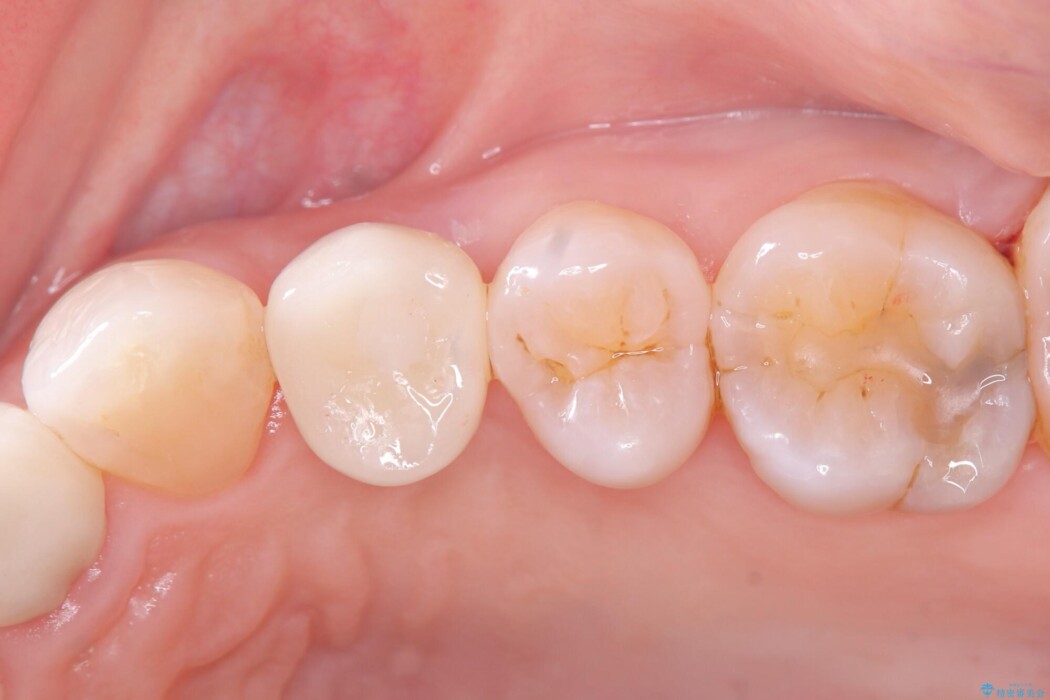

被せ物を除去し、マイクロスコープにて内部を強拡大で確認したところ、歯の根の深い位置まで真っ直ぐにひびが入っていることを確認し、保存が不可能な状態であったため抜歯をすることとなりました。

インプラント治療後は「長年悩まされた痛みから解放され、自分の歯と同じように食事ができるようになった」と喜んでいただけました。